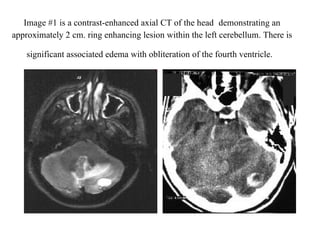

von Hippel-Lindau disease HBs of the CNS Figure 1 MRI scan of two small solid cerebellar HBs (arrows) in a 52-year-old VHL patient. Figure 2  MRI scan of a typical cystic cerebellar HB in a 39-year-old non-VHL patient. Figure 3 Two solid brain stem HBs and a cystic HB in the cervical spine in a 32-year-old VHL patient. Figure 4  An HB in cervical spine in a 21-year-old VHL patient: MRI with contrast (a), superselective angiography before (b) and after (c) preoperative embolization. Figure 5 Two small spinal HBs in the thoracic region (a and b) in the same patient as in Figure 4, three years later. Figure 6 A large solid recurrent HB 11 years after the primary total removal in a 66-year-old non-VHL patient.

Copyright © 2007 by the American Roentgen Ray Society Herwick, S. et al. Am. J. Roentgenol. 2006;187:W472-W480 --52-year-old man with von Hippel-Lindau disease and pancreatic mass diagnosed as serous cystadenoma on basis of findings at previous fine-needle aspiration